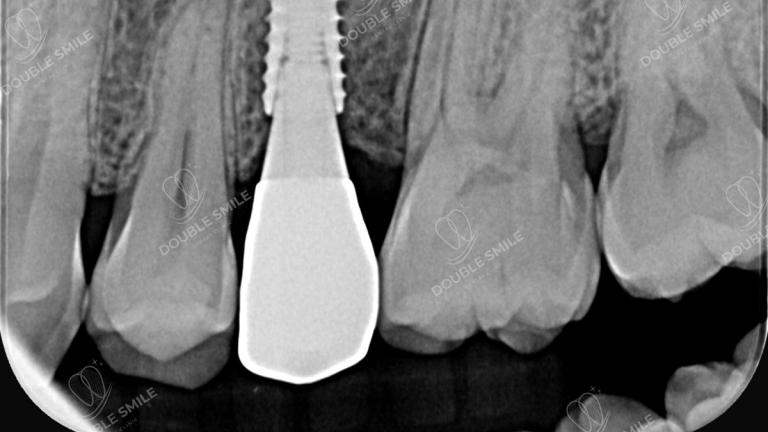

After